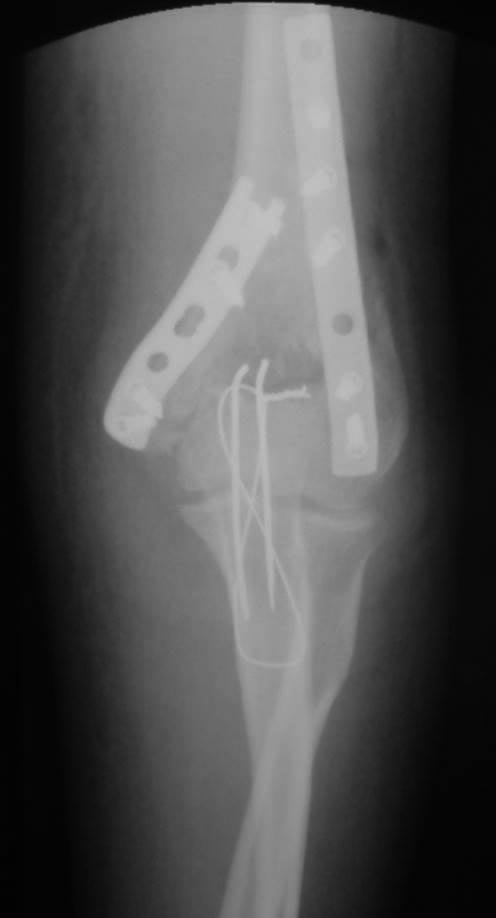

Как обещал, выкладываю послеоперационные (на следующий день после операции) фото. Заранее прошу слишком проксимальную остеотомию локтевого отростка не ругать. Обычно делаю дистальнее.

А перелома головки луча на послеоперационных снимках даже не видно(возвращаясь к исходной теме)

Простите, маленький вопрос. Обе пластины по задней поверхности. Трансфрактурного винта нет. Как достигли компрессии между отломками? (не с целью придраться)

Медиальная пластина изогнута спирально и ее дистальный конец лежит на заднемедиальной поверхности, в соответствии с расположением наиболее крупного фрагмента внутреннего надмыщелка. А про стягивающий винт уже написано ниже. Блок плечевой кости цел, соответственно трансфрактурный винт здесь не нужен. Если я правильно понял вопрос. И еще интересно, какая связь между расположением пластин только по задней поверхности и компрессией между отломками?

Уточню, надмыщелки(оба) и блок. Винтов нет ,пластины сзади. Компрессия на инструменте?

На боковой проекции петля проволоки лежит не совсем на кости. При разработке сустава локтевой отросток может немного сместиться. А плечевая вроде хорошо стоит

Петля проволоки вовсе не лежит на кости. Также, как и кончики спиц, она лежит поверх сухожилия трицепса. Зачем же скелетировать локтевой отросток? Главное здесь, по-моему, чтобы петля и кончики спиц располагались рядом. Тогда можно будет легко удалить всю конструкцию через сантиметровый разрез.